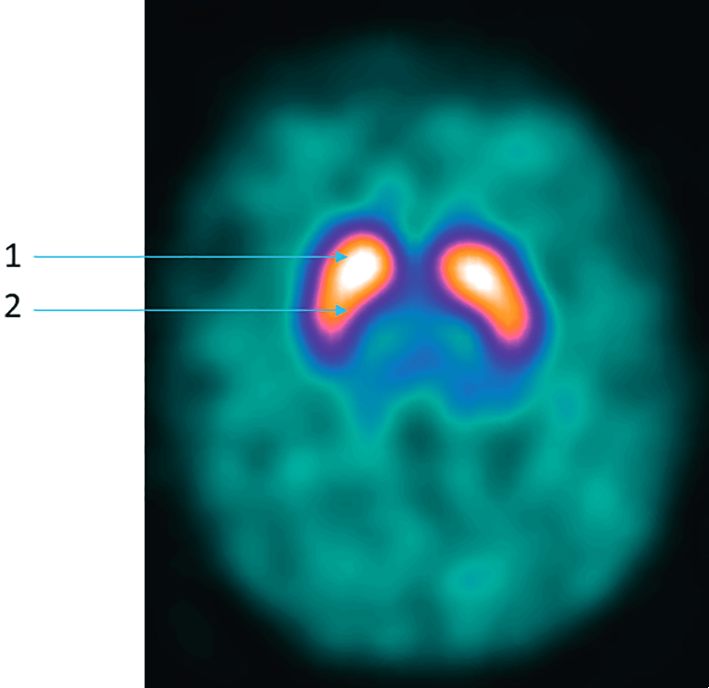

Fig. 132.6 Scintigraphie au DaTSCAN®.

Coupe axiale normale de tomoscintigraphie cérébrale au 123I-ioflupane montrant la distribution du traceur sur les striata avec une forme de virgule symétrique (la flèche 1 désigne le noyau caudé, la flèche 2 le putamen, la fixation sur le reste du cortex cérébral est faible).